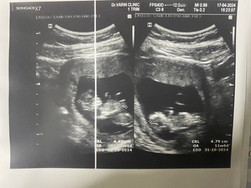

ใบชาว10w6d แต่นับจาก ปจด.ครั้งสุดท้าย11w6d😂

10weeks 4days